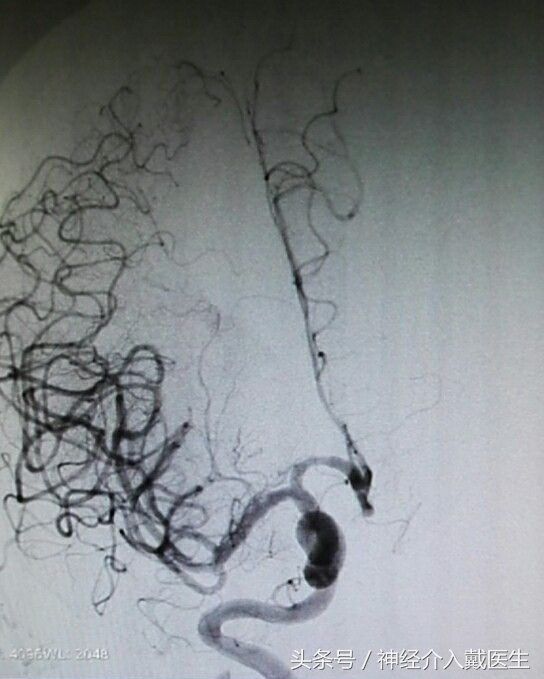

支架机械取栓治疗是目前治疗急性脑梗死的最为先进的技术手段,和溶栓治疗相比具有安全性高、作用显著和时间窗长等优点,目前已在国内外大型医疗中心普及。支架机械取栓是将一条直径0.3毫米左右的导丝从患者股动脉穿入体内,在透视监示下通过脑内大血管中的血栓进行定位,再用微导管将镍钛合金的取栓支架输送到血栓部位,释放支架后,镍钛合金支架自动膨胀展开,形成圆柱形网状结构,与血管壁贴合、嵌入血栓。术者将取栓装置抽离,栓子同时被拽出体外。

机械取栓具有血管再通率高、脑出血发生率低、再通时间、治疗时间窗延长等优点。目前很多学者认为,只要MRI显示存在较大的缺血半暗带,就应该积极开通血管,但治疗时间窗有待进一步研究。机械取栓也存在因手术准备及操作延迟血管再通、对操作人员及设备要求较高等缺点。